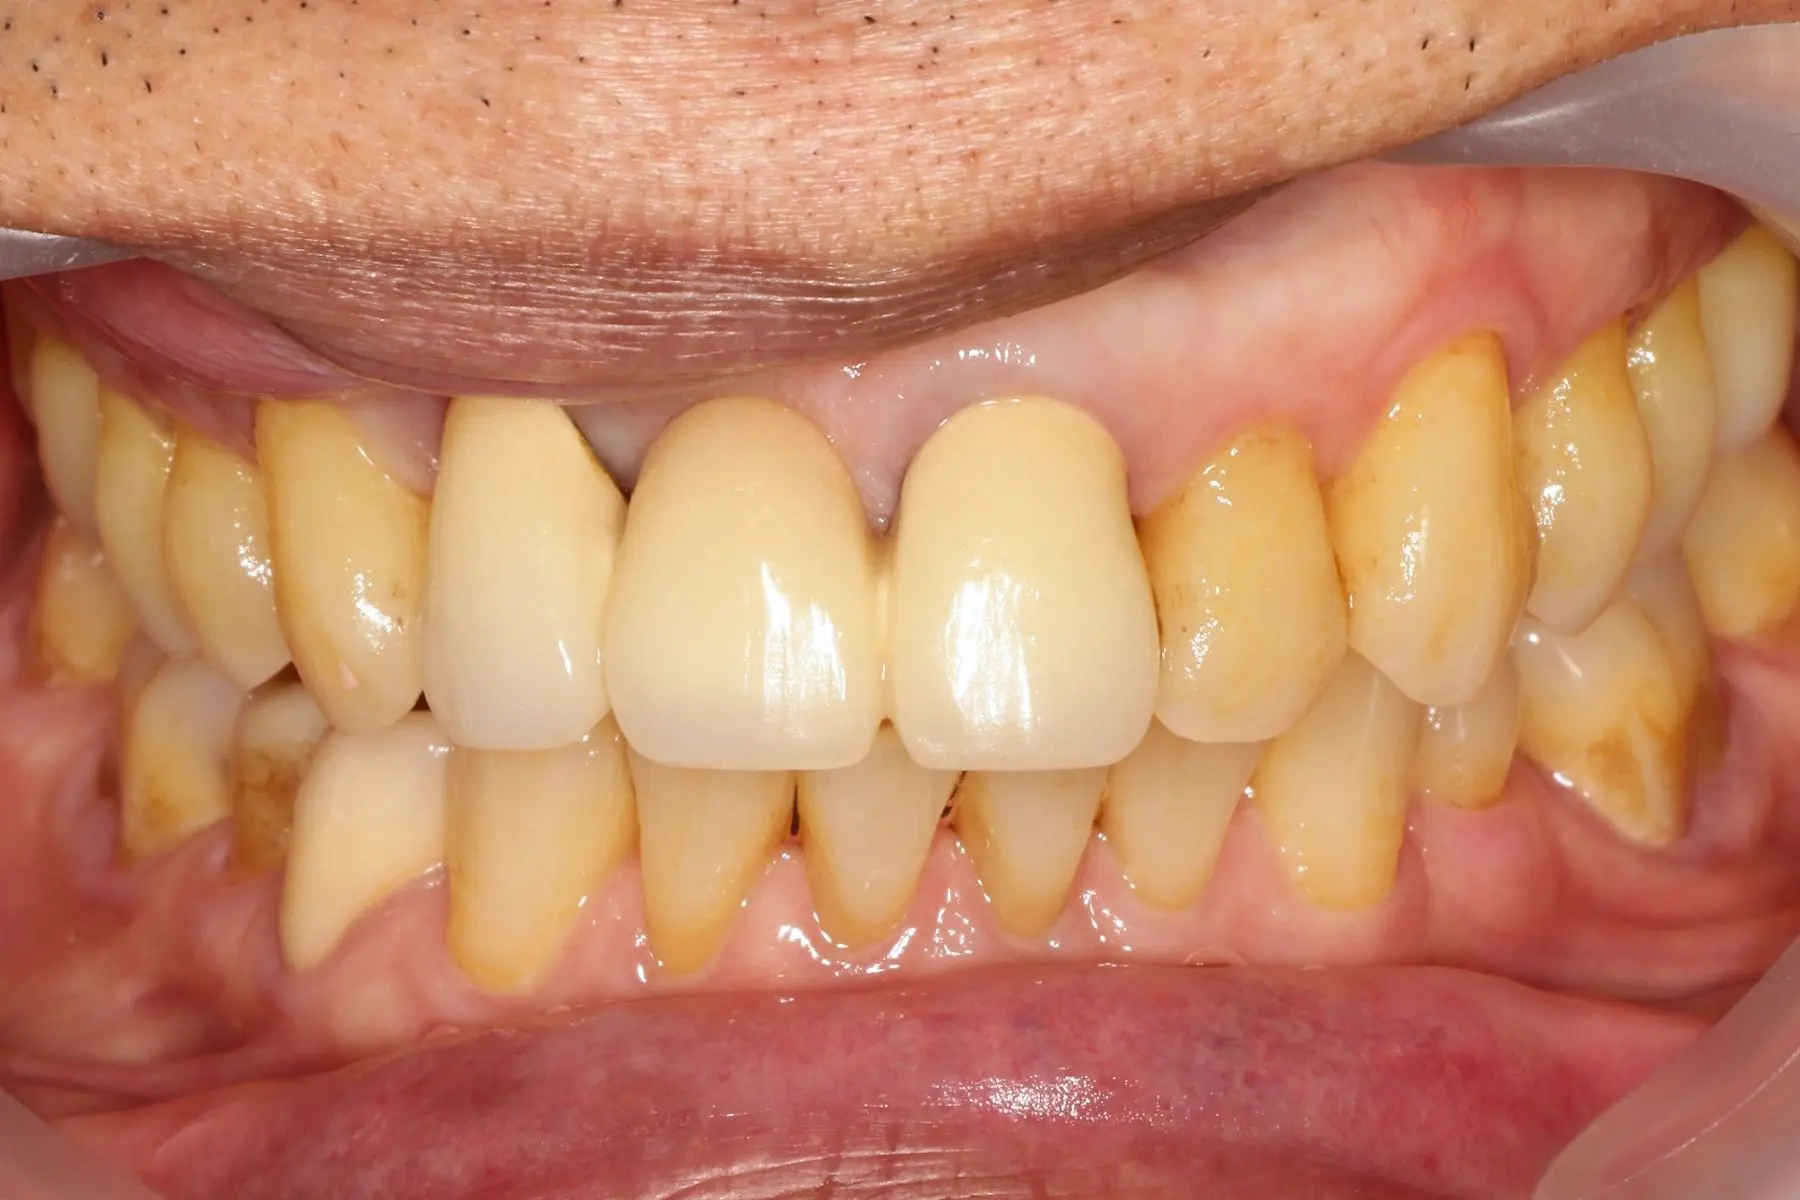

• 術前 42

術後 40

牙周治療

主治醫師

• 鍾國耀

治療時間

三次療程

主訴

右上前牙牙齦反覆腫脹化膿